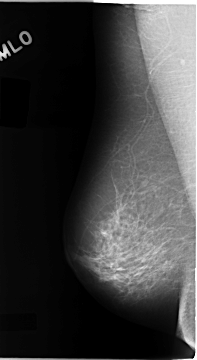

C_0108_1.RIGHT_MLO

RIGHT_MLO LINES 4672 PIXELS_PER_LINE 2560 BITS_PER_PIXEL 12 RESOLUTION 50 NON_OVERLAY